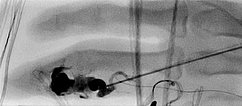

Angiographic control of the right hand with catheter injection from transarterially via the ulnar artery. Complete devascularization of the AVM nidus. No fast-flow shunts can be angiographically detected. The treated AVM with occluded nidus is thus resectable.

Fluoroscopic view of the cast after successful nidus embolization of the AVM. To improve the overview for surgical planning, this image is also shown without subtraction with visible bone.